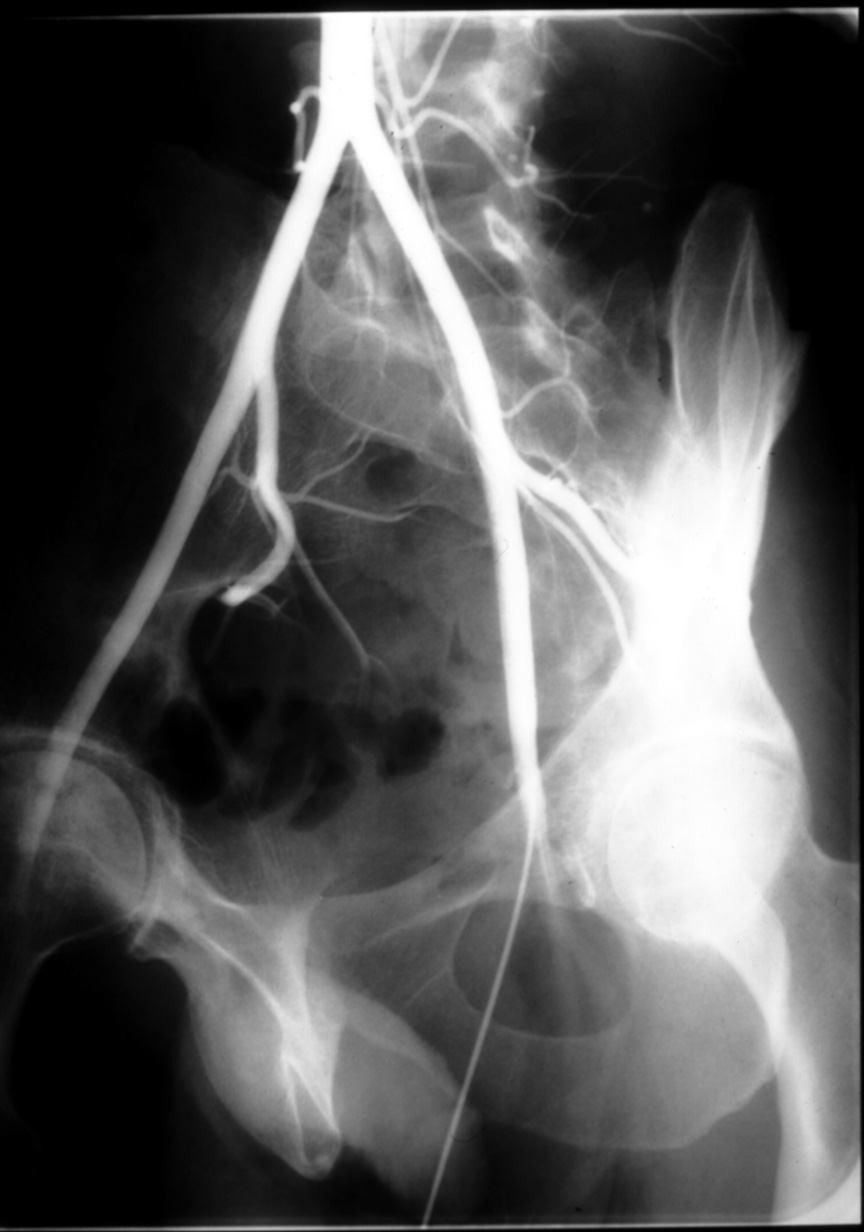

The Structural Basis of Medical Practice

The Pennsylvania State University ©2000

College of Medicine